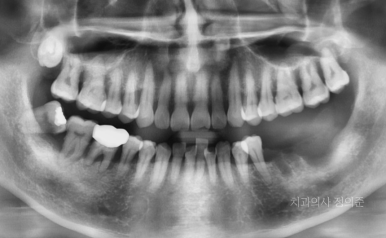

타치과에서 발치하시고 1주일 뒤에 내원하셨을 때의 파노라마 (좌측 사진)

첫 내원 당시의 왼쪽 아래 어금니 부위의 상태 (우측 사진)

2023. 7

내원 당시 왼쪽 아래 큰 어금니들을 발치하신 상태셨고,

1주일 정도 밖에 되지 않아 아무래도 잇몸은 회복 과정에 있는 상태였습니다.

정확한 진단과 치료 계획 수립을 위하여 CT 촬영을 진행하였습니다.